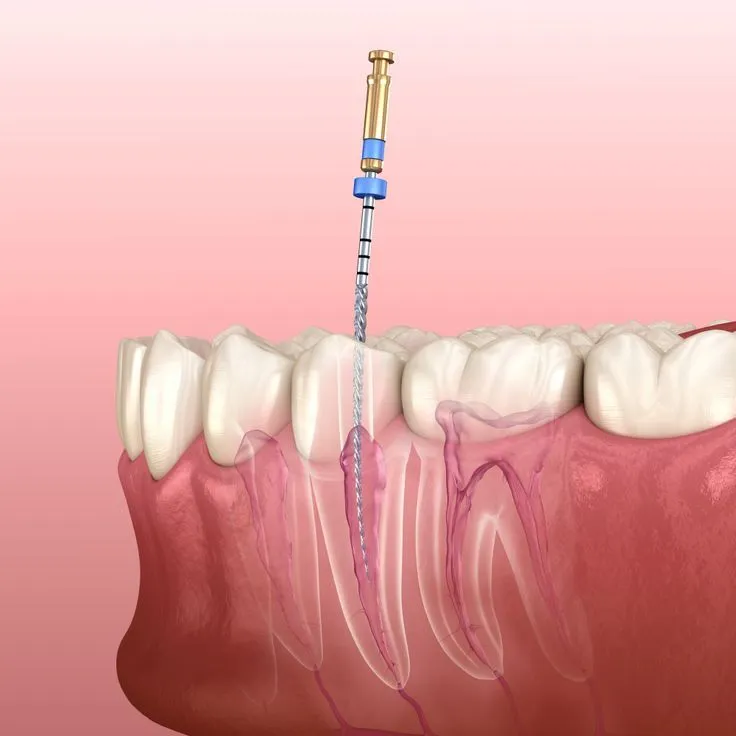

پیش از آنکه وارد مبحث ترمیم ریشه مدرن شویم، بهتر است مفهوم پایهای درمان ریشه را مرور کنیم. زمانی که پوسیدگی دندان به عمق زیادی نفوذ کرده و به پالپ (عصب) دندان میرسد، التهاب یا عفونت ایجاد میشود. در این حالت دندانپزشک با انجام درمان ریشه، بافت عصبی آلوده را خارج کرده و فضای داخلی دندان را ضدعفونی و پر میکند.

در این مرحله از ابزارهای نیکل-تیتانیوم انعطافپذیر برای تمیز کردن کانال استفاده میشود. - شستوشو با سیستمهای التراسونیک و ضدعفونی کامل

در روش مدرن، از سیستمهای التراسونیک برای شستوشوی کانالها استفاده میشود. این امواج موجب حذف کامل باکتریها و باقیماندههای عفونی میشوند. مواد شستوشو مانند EDTA و هیپوکلریت سدیم فعالشده نیز در این فرآیند نقش مهمی دارند. - پر کردن کانال با مواد زیستی نوین

CBCT با ایجاد تصویر سهبعدی از ریشه دندان، امکان تشخیص دقیق و درمان بدون خطا را فراهم میکند. این فناوری بهخصوص در مواردی که ساختار ریشه پیچیده است، بسیار مفید است. - ابزارهای نیکل-تیتانیوم (NiTi)

این ابزارها بسیار انعطافپذیر بوده و در کانالهای باریک یا خمیده بدون آسیب به دیواره دندان حرکت میکنند. در نتیجه درمان ایمنتر و مؤثرتر انجام میشود. - نرمافزارهای هوشمند و دیجیتال دنتیستری